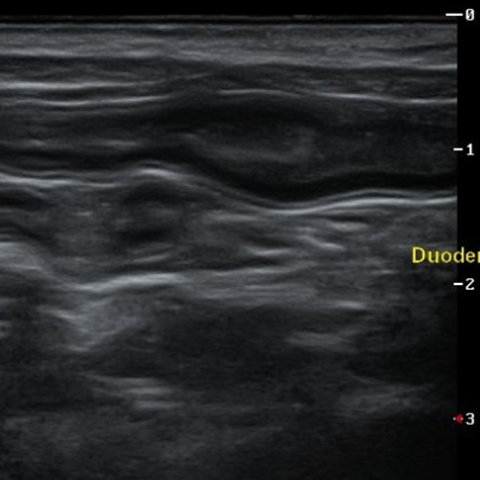

°í¾çÀÌ ¼¼µ¿ÀÌ¿°(Triaditis)

°í¾çÀÌ¿¡°Ô¼ ²Ï ÈçÇÏÁö¸¸ Áø´ÜÀÌ ³ª¿ÔÀ» ¶§ º¸È£ÀںеéÀÌ ¸¹ÀÌ »ý¼ÒÇØ ÇϽô ÁúȯÀä, °£´ÜÈ÷ ¸»ÇØ ´ã°ü°£¿°, ÃéÀå¿°, Àå¿°(¿°Áõ¼ºÀåÁúȯ)ÀÌ µ¿½Ã¿¡ ¹ß»ýÇÏ°Ô µÈ »óÅÂÀÔ´Ï´Ù. ±¸Åä, ¼³»ç, ±â·Â ¹× ½Ä¿åÀúÇÏ °°Àº Áõ»óÀÌ ³ªÅ¸³ª°í ½ÉÇÑ °æ¿ì Ȳ´Þ°ú ºóÇ÷±îÁö ³ªÅ¸³¯ ¼ö ÀÖ´Â ÁßÁõ ÁúȯÀä, °í¾çÀÌ´Â ³»ºÎ Àå±âÀÇ ÇØºÎÇÐÀû ±¸Á¶ »ó ´ã°ü°ú ÃéÀå°üÀÌ ½ÊÀÌÁöÀå¿¡¼ ÇÕÃÄÁö°Ô µÇ´Âµ¥, ÀÌ·Î ÀÎÇØ °£À̳ª ÃéÀå, ¼ÒÀå ¾î´À ÇÑ °÷¿¡ ¿°ÁõÀÌ »ý°Üµµ °¡±î¿î ÁÖº¯ Àå±â¿¡±îÁö ÀÌȯ µÇ¾î Àü½ÅÀûÀÎ ÁúȯÀ» ÀÏÀ¸Å°°Ô µË´Ï´Ù.

°í¾çÀÌÀü¿°¼ºº¹¸·¿°Àº °í¾çÀÌÄڷγª¹ÙÀÌ·¯½º°¡ ¿øÀÎü·Î, °í¾çÀÌ Ã¼³»¿¡ Àẹ »óÅ¿´´ø Äڷγª¹ÙÀÌ·¯½º°¡ ¸Íµ¶¼ºÀ» °¡Áø ¹ÙÀÌ·¯½º·Î º¯À̵Ǿî Àü½Å Àå±â¿¡ ¿°ÁõÀ» ÀÏÀ¸Å°°í, ºóÇ÷, Ȳ´Þ, Èä¼ö, º¹¼ö, ½Å°æ Áõ»óÀ» ÀÏÀ¸Å°´Â Àü¿°¼º ÁúȯÀÔ´Ï´Ù. Àü¿°¼ºº¹¸·¿°Àº ÀÓ»ó Áõ»ó, Ç÷¾× °Ë»ç, Èä/º¹¼ö PCR °Ë»ç, ¹æ»ç¼±, ÃÊÀ½ÆÄ, CT¸¦ ºñ·ÔÇÑ ¿µ»ó °Ë»ç °á°ú¸¦ Á¾ÇÕÀûÀ¸·Î ÆÇ´ÜÇÏ¿© Áø´ÜÇÏ°Ô µË´Ï´Ù. ÀÏ´Ü È®ÁøÀÌ µÇ¸é Ç×¹ÙÀÌ·¯½ºÁ¦¸¦ Åõ¿©ÇÏ´Â °Í¸¸ÀÌ À¯ÀÏÇÑ Ä¡·á ¹æ¹ýÀÔ´Ï´Ù.